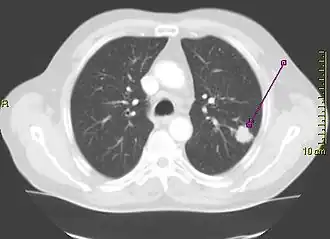

A "lung window" CT scan showing a lung cancer in the left lung

Computed tomography of the chest or chest CT is a group of computed tomography scan protocols used in medical imaging to evaluate the lungs and search for lung disorders.

Contrast agents are sometimes used in CT scans of the chest to accentuate or enhance the differences in radiopacity between vascularized and less vascularized structures, but a standard chest CT scan is usually non-contrasted (i.e. "plain") and relies on different algorithms to produce various series of digitalized images known as view or "window". Modern detail-oriented scans such as high-resolution computed tomography (HRCT) is the gold standard in respiratory medicine and thoracic surgery for investigating disorders of the lung parenchyma (alveoli).